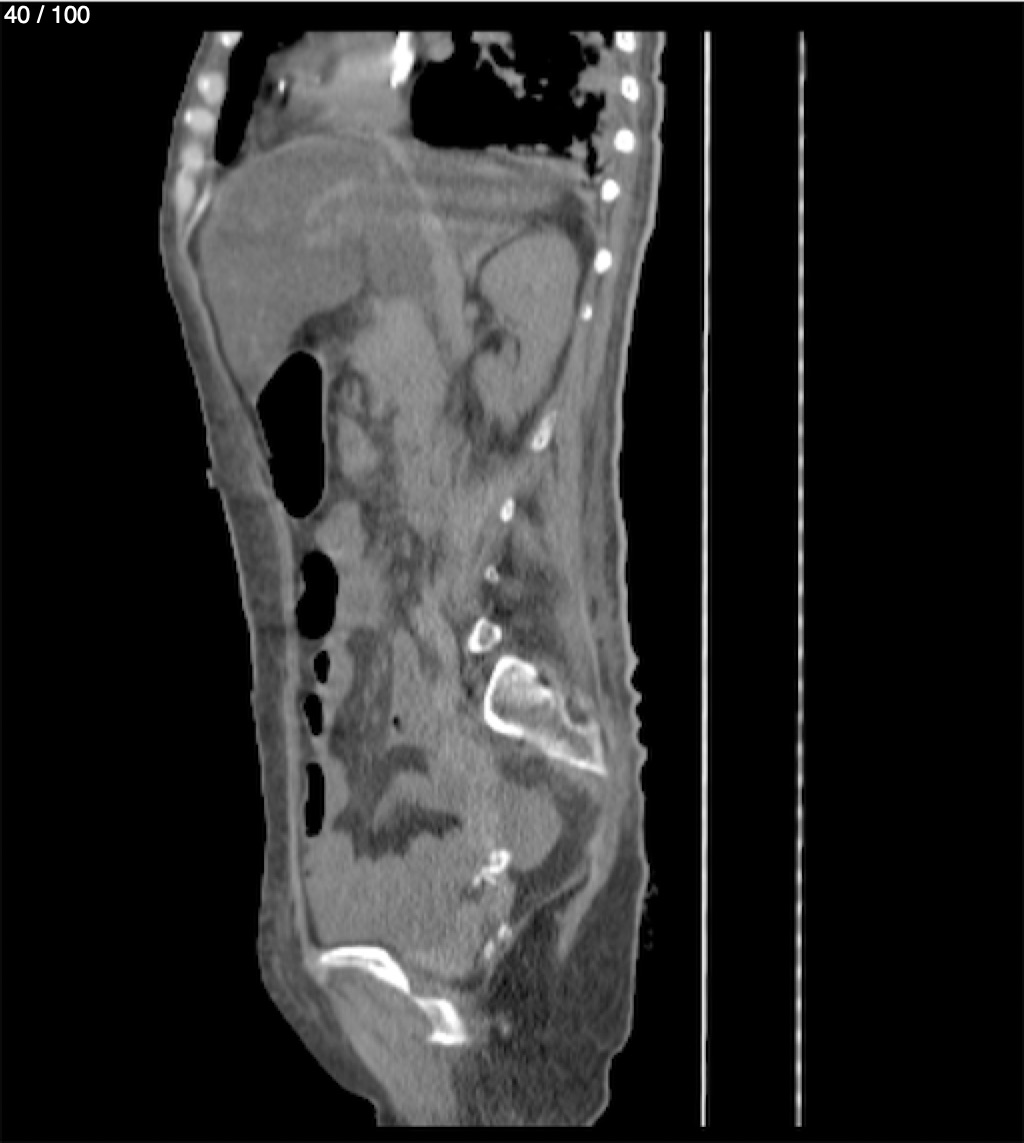

Hilda Geronimo Mendez 60A - T.C Abdomen Simple